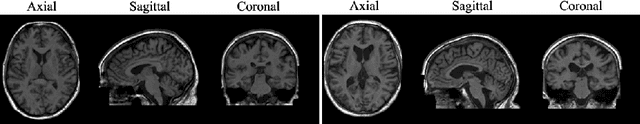

Abstract:Human anatomy, morphology, and associated diseases can be studied using medical imaging data. However, access to medical imaging data is restricted by governance and privacy concerns, data ownership, and the cost of acquisition, thus limiting our ability to understand the human body. A possible solution to this issue is the creation of a model able to learn and then generate synthetic images of the human body conditioned on specific characteristics of relevance (e.g., age, sex, and disease status). Deep generative models, in the form of neural networks, have been recently used to create synthetic 2D images of natural scenes. Still, the ability to produce high-resolution 3D volumetric imaging data with correct anatomical morphology has been hampered by data scarcity and algorithmic and computational limitations. This work proposes a generative model that can be scaled to produce anatomically correct, high-resolution, and realistic images of the human brain, with the necessary quality to allow further downstream analyses. The ability to generate a potentially unlimited amount of data not only enables large-scale studies of human anatomy and pathology without jeopardizing patient privacy, but also significantly advances research in the field of anomaly detection, modality synthesis, learning under limited data, and fair and ethical AI. Code and trained models are available at: https://github.com/AmigoLab/SynthAnatomy.